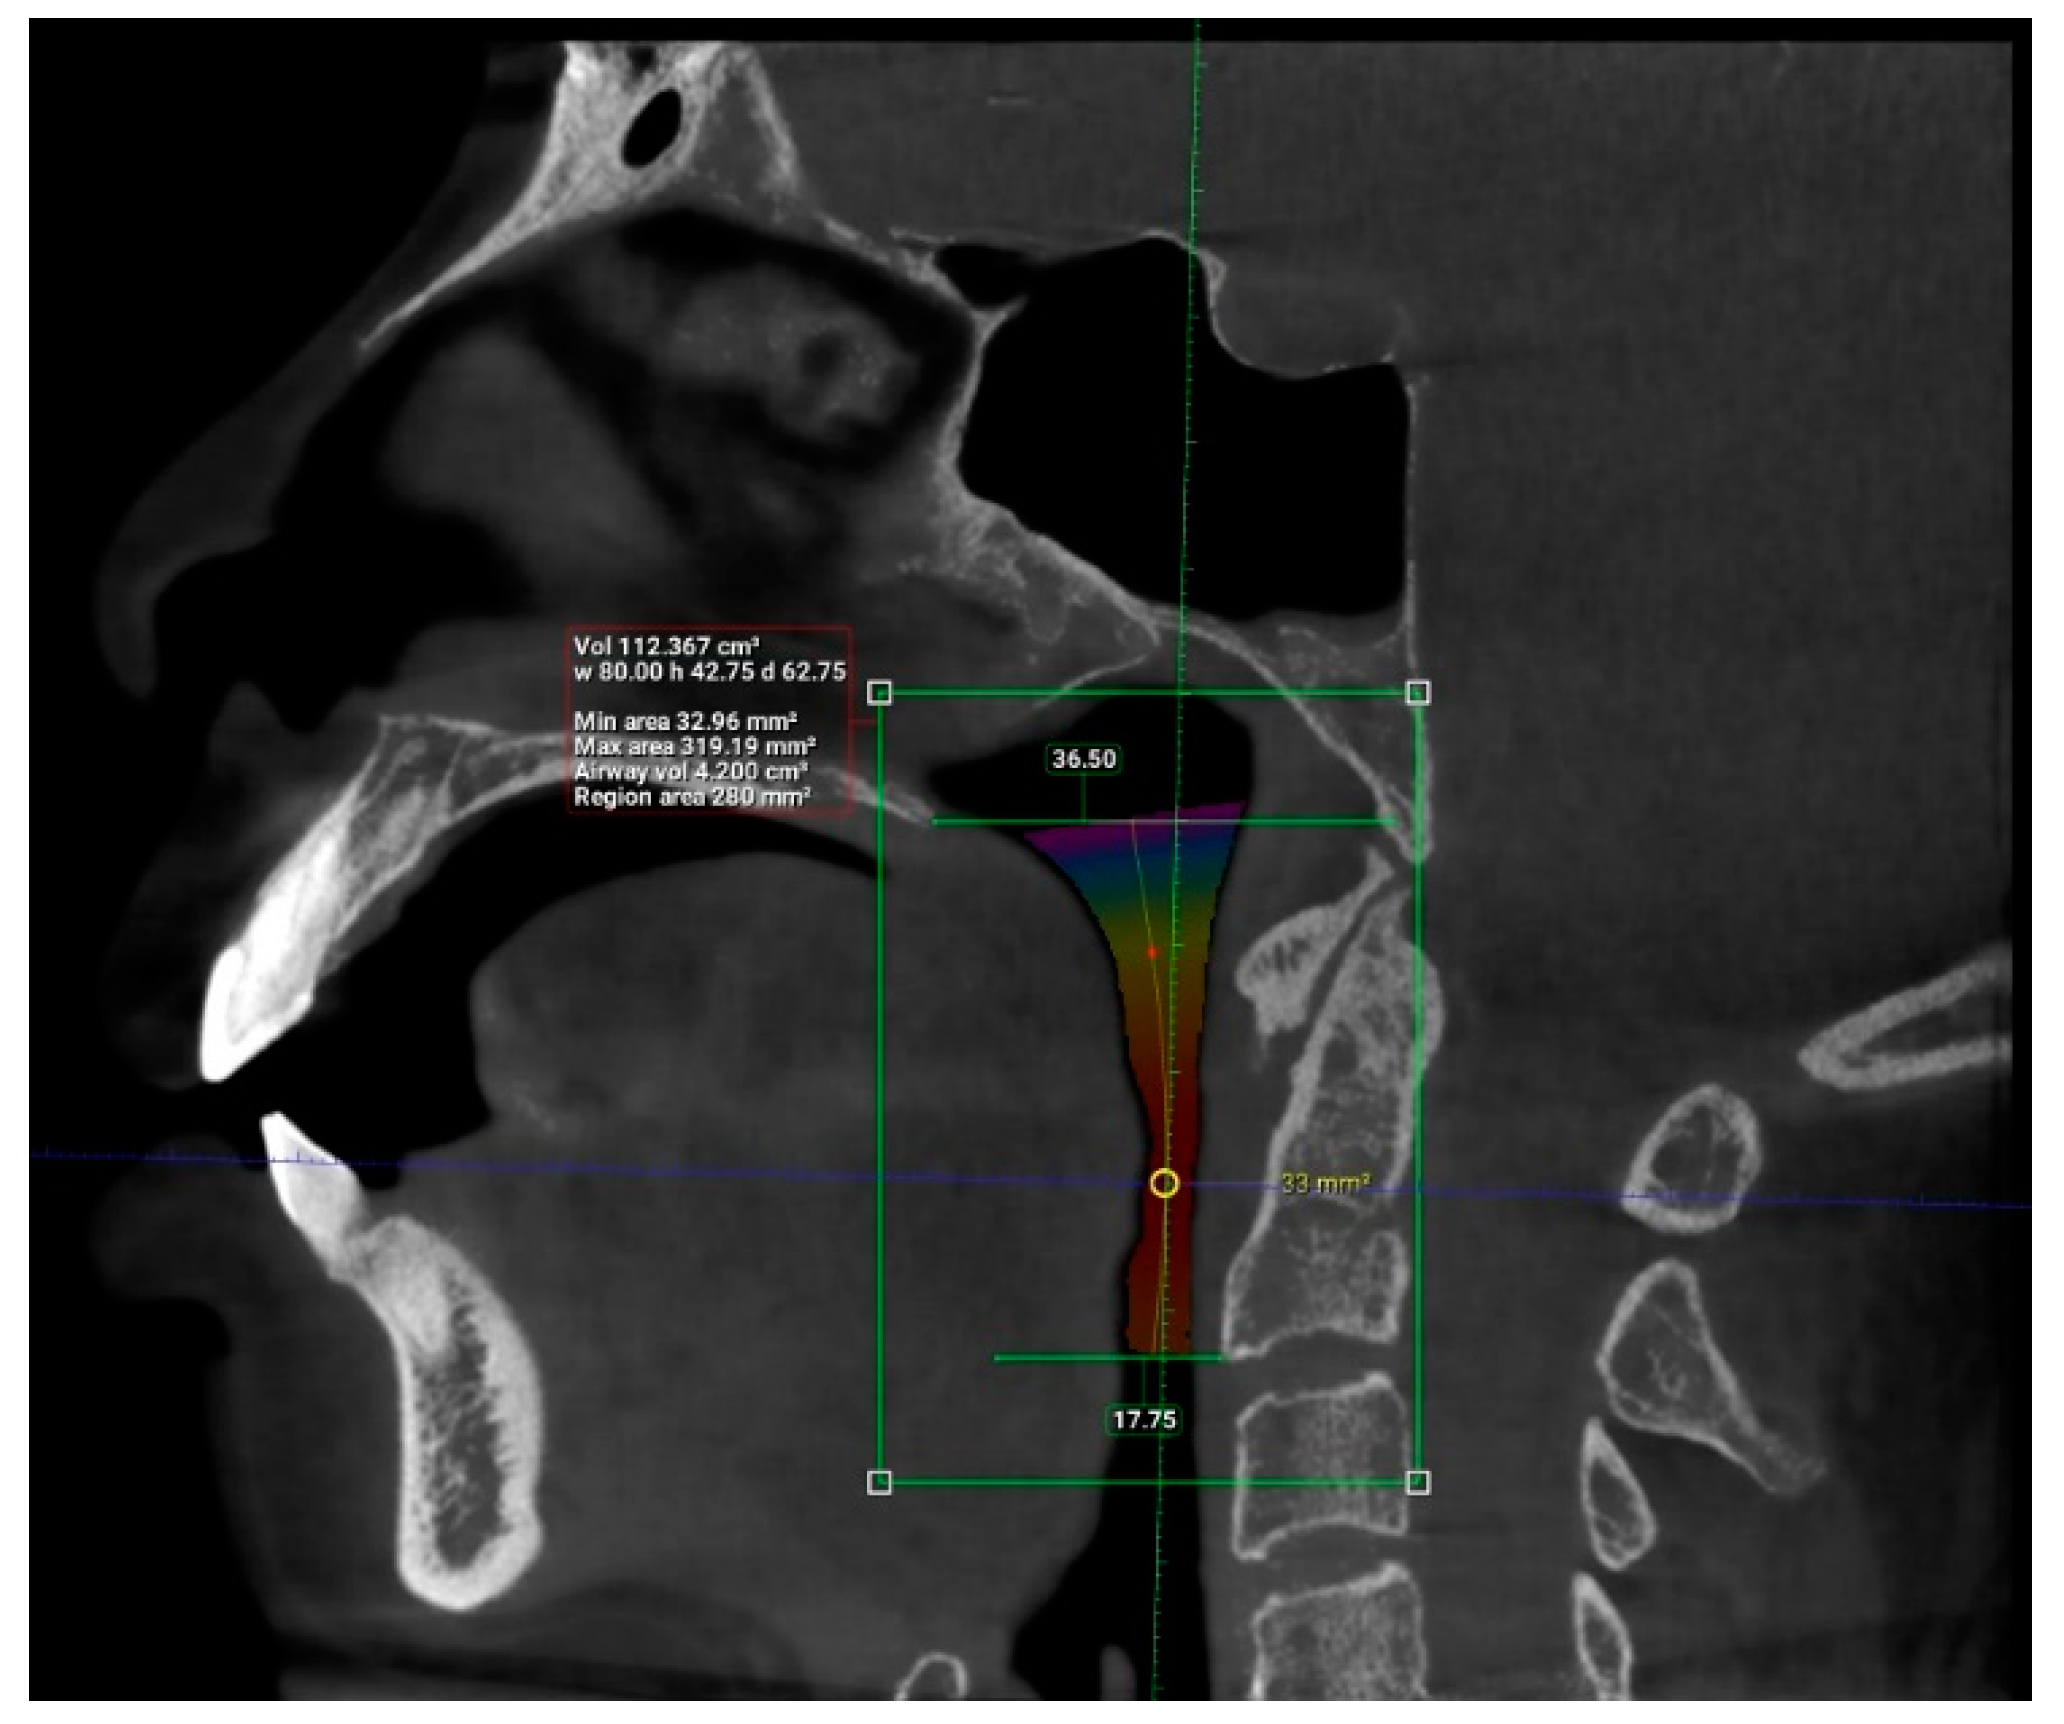

| Length (mm) | 101 | 29.93 | 55.75 | 42.63 | 6.24 |

| Total volume (cm3) | 101 | 94.58 | 173.45 | 131.67 | 17.91 |

| Average volume (cm3) | 101 | 3.34 | 32.09 | 11.10 | 5.21 |

| Antero-posterior (mm) | 101 | 1.00 | 14.50 | 6.44 | 3.19 |

| Width (mm) | 101 | 8.00 | 37.00 | 21.69 | 6.54 |